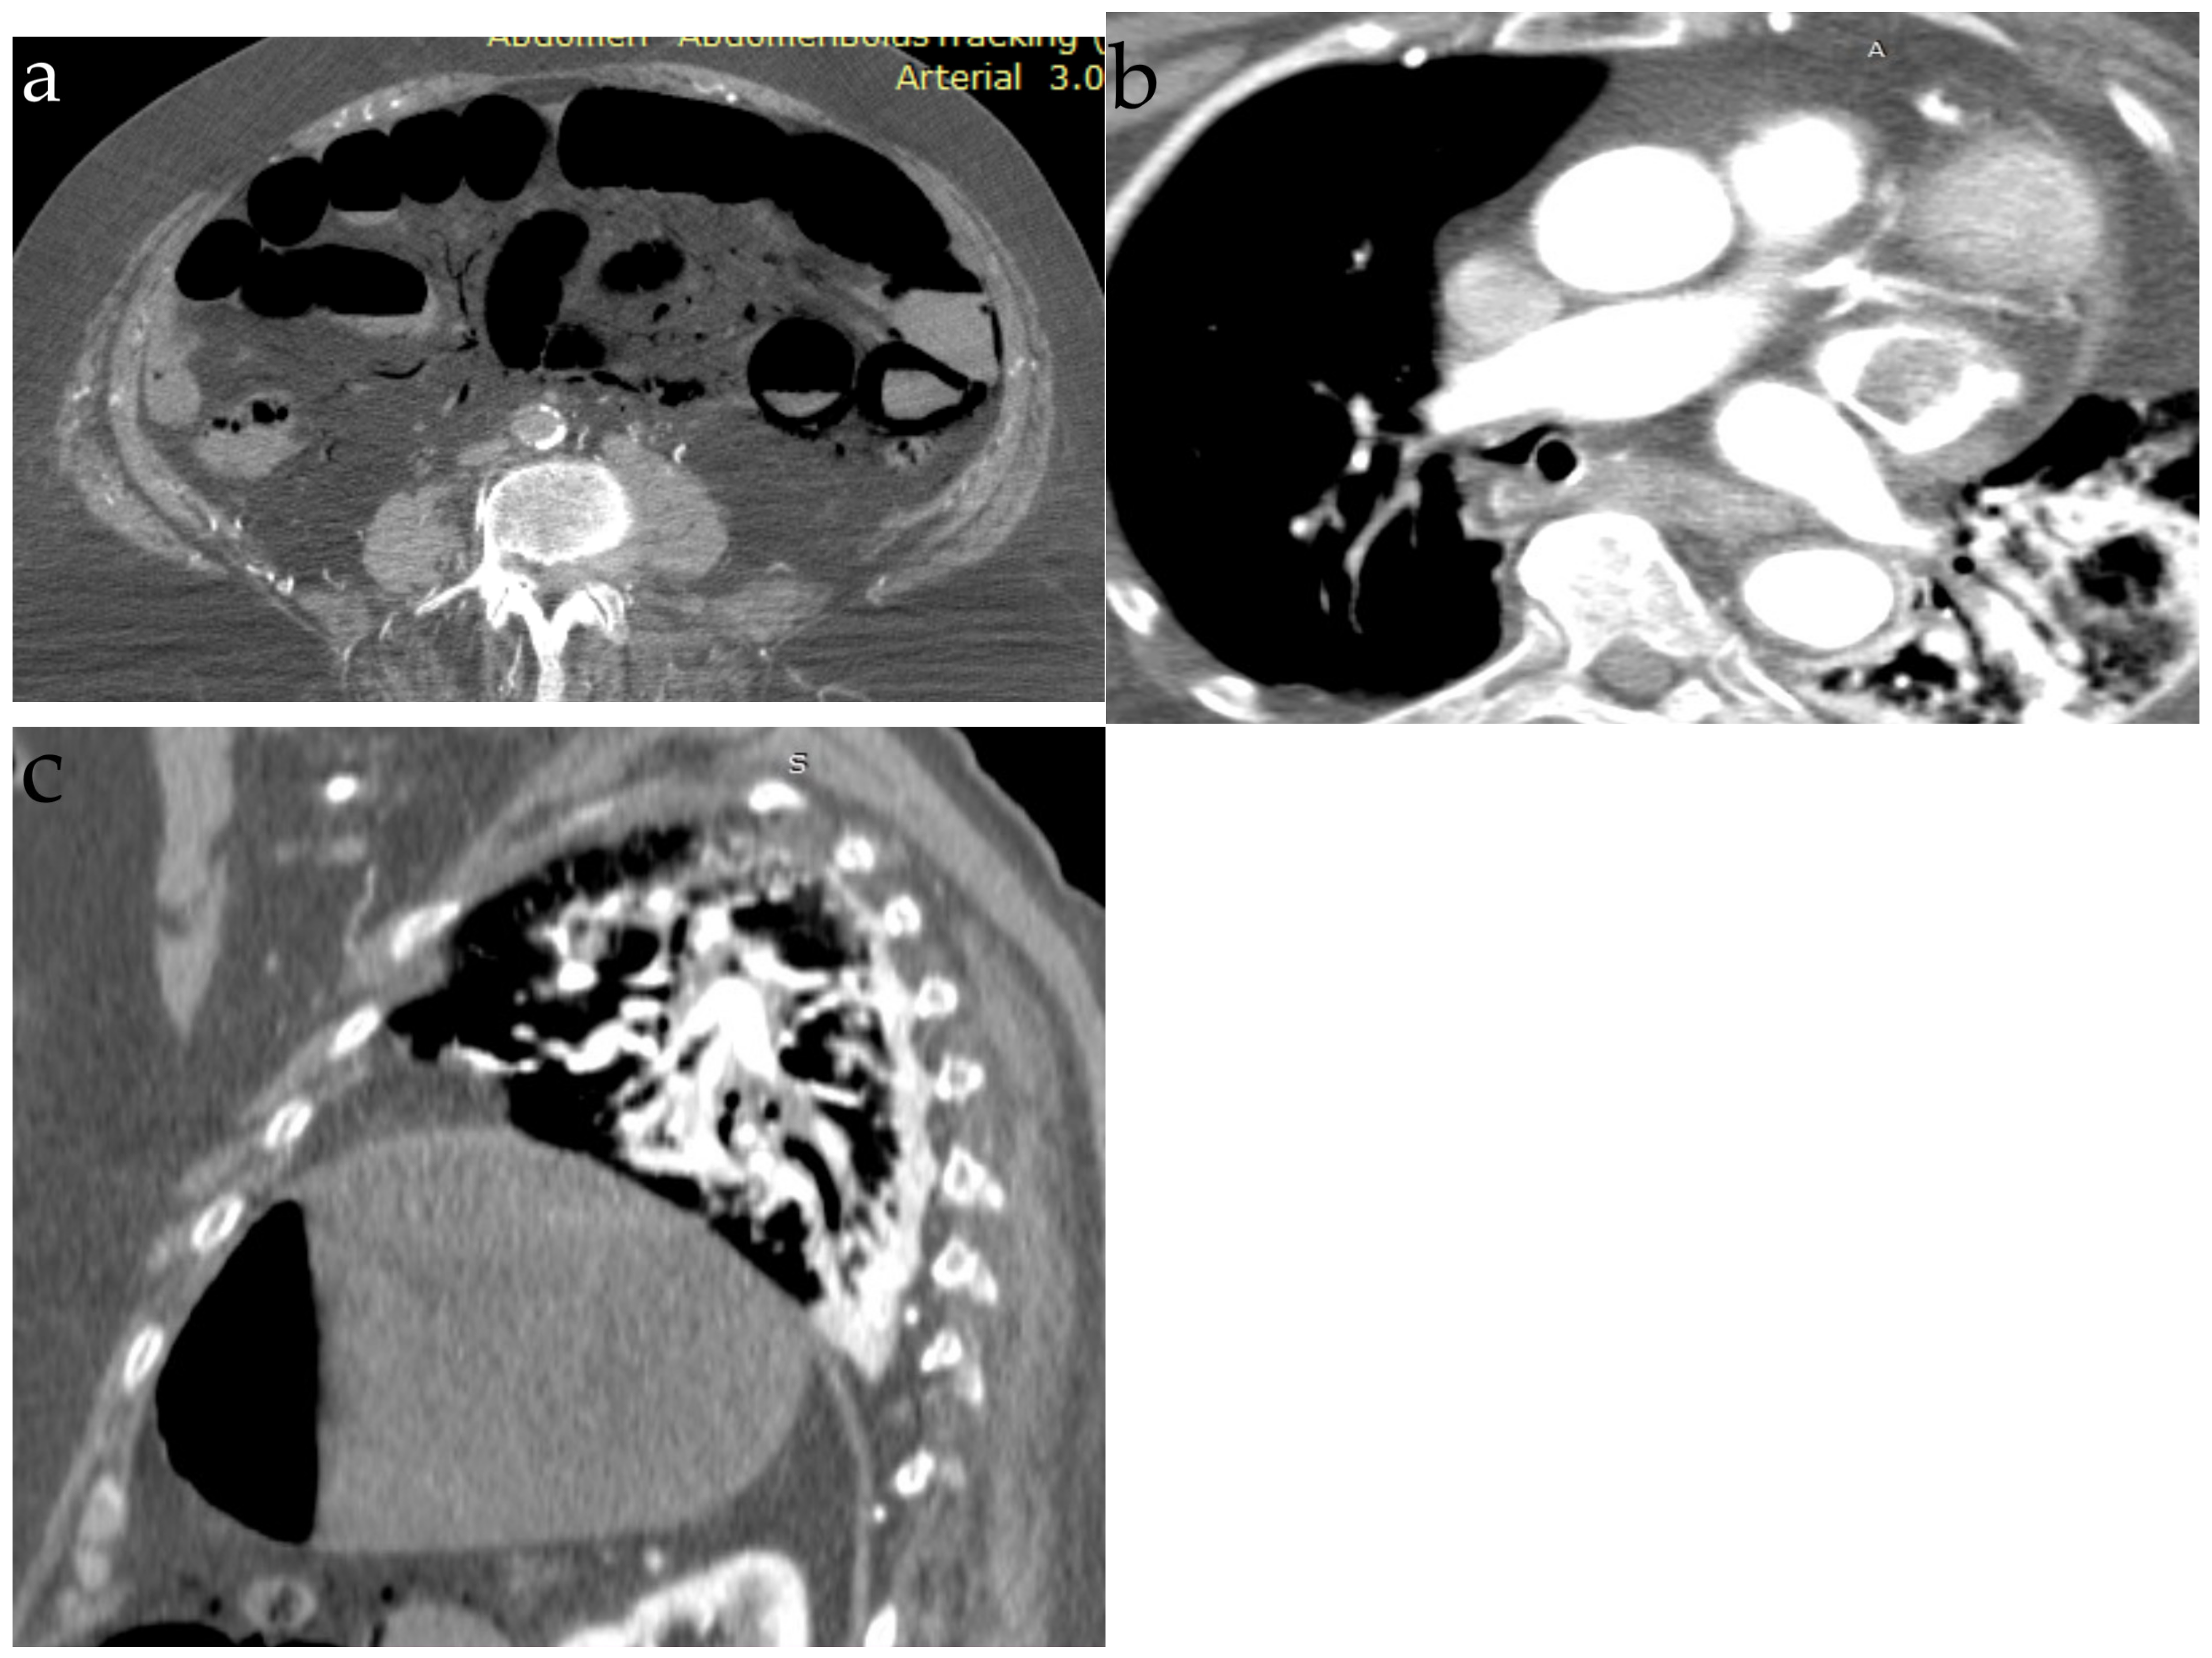

6. Tumor Embolism

| Computer tomography | Small amount of air in the main pulmonary artery, on the right heart or systemic veins; in severe cases, pulmonary hypertension and right heart strain are found | Ground-glass opacities, interlobar septal thickening with the pattern of “crazy paving” | Diffuse bilateral ground-glass opacities | Bilateral lung nodules, located mainly in the peripheral lung areas and in the lower lobes, mediastinal or hilar lymphadenopathy, a dilated pulmonary branch (mycotic aneurysm) and feeding vessel sign | The classic finding (affected centrilobular arteries) is an image of “tree-in-bud”; in cases where the main arteries are affected, the findings are filling defects that resemble acute or chronic pulmonary emboli |